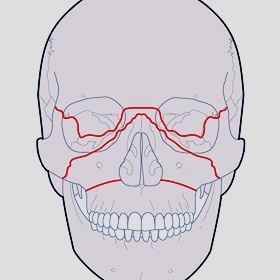

Defects affecting the upper and lower jaw can be seen in a variety of patients. With maxillofacial trauma being very common, and the culprit for many of these injuries, the treatment of facial trauma and reconstruction of defects goes hand-in-hand. An injury can cause damage to the jaw, resulting in bone loss, or the problem may be a result of flawed developmental processes. In some patients the jaw may not develop fully in certain regions. Some medical conditions, such as cancer and infections of the head and neck, can lead to jaw deformities and defects.

Severe facial injuries can be seen in a variety of circumstances. Car accidents and assault are the leading causes seen in facial injury, others include sports and falls. When the facial structures are damaged by trauma, an oral and maxillofacial surgeon is often involved in the treatment to repair and reconstruct that damage. When teeth are lost as a result of an injury, they can also be replaced with dental implants as part of the reconstruction.

Immediate intervention is typically required in most cases of maxillofacial trauma. If broken bones are involved and displaced, those fractures must be returned to the original position and stabilized in place until the healing process is complete. Once the initial injury is treated and stabilized, patients often need ongoing follow-up. Additional procedures may be needed in order to return the patient to form and function.

Regardless of the cause of the defect, Dr. Duraini can help restore the patient to normalcy. The patient may elect to undergo reconstructive surgery to restore esthetics or function, or both. Every patient is thoroughly evaluated to determine the best type jaw reconstruction. Visual inspection and examination by Dr. Duraini along with advanced imaging techniques available at Texas Maxillofacial Surgery will help in making the decision.